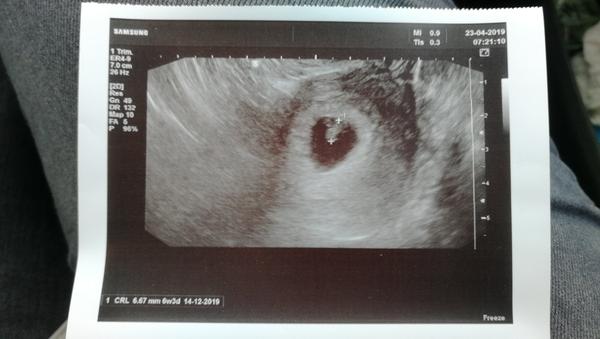

Ve čtvrtek jsem začala krvacet a jela jsem na pohotovost. (5+5tt) Tam mi doktorka udělala vyšetření, potvrdila, že se zde nachází gestacni vacek o rozměru cca 9mm a v něm jen malá tečka jako zloutkovy váček, žádný náznak plodu. Napsala mi ascorutin a do záznamu napsala missed AB, ale mi o tom nic neřekla. Krvacela jsem celkově asi 2 hoďky - světla krev, ale max. na 1 vložku - ani to ne a od té doby nic. Samozřejmě, jak jsem viděla missed AB, tak jsem si doma pobrečela.

V úterý jsem šla na plánovanou prohlídku k mé gynekolozce. Ta mi dělala vyšetření (6+3tt) a viděla už i plod, který měl cca 2,2mm, rikala, ze je velmi malý a že nedokáže určit, jestli mu bije srdíčko nebo je to jen můj tep. Říkala, že je plod menší, než by měl být v 6+3tt, ale jelikož mám delší cykly (30+dni) říkala, že mohlo dojít k oplodnění později a že mám přijít znova příští úterý. Když se dívala na záznam od paní doktorky z nemocnice, říkala, ze určit missed AB bylo strašně brzo. Po tomto vyšetření jsem trochu špinila (ale jen při utřeni a velmi málo jen takový hnědý odstín).